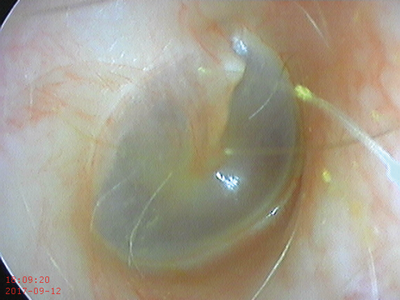

Endoscope-i - otoscopy image.

Endoscope-i **BEST VALUE**

Type: Endoscope adapter for iPhone 5/6/7/8/X (requires endoscope + light source) Captures images + videos

Cost: £99

Image quality: 87%

Field of view: 100%

Ease of use: 58%

Comments: Overall excellent image quality and field of view (tested with iPhone 7). Somewhat awkward for photo use due to the distance of the capture button from the endoscope attachment position. This resulted in a tendency for movement at the moment of photo taking. This was not a problem for videos which could be started and then a more comfortable grip found.